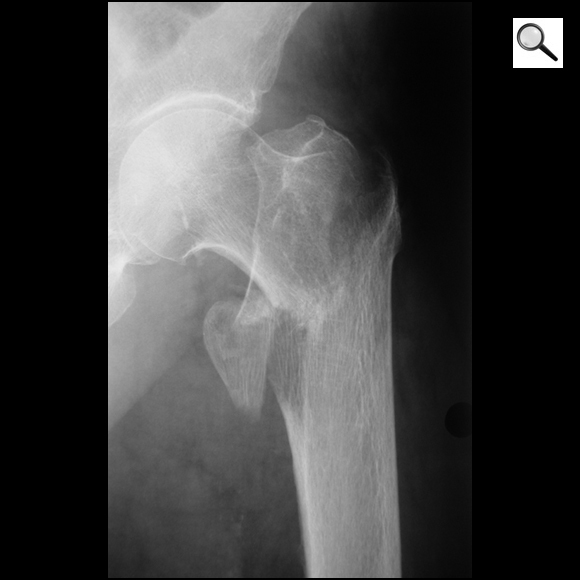

Quel diagnostic? Quel traitement?

Fracture per-trochantérienne fermée de l’ES du fémur gauche

ttt= vis plaque ou clou gamma